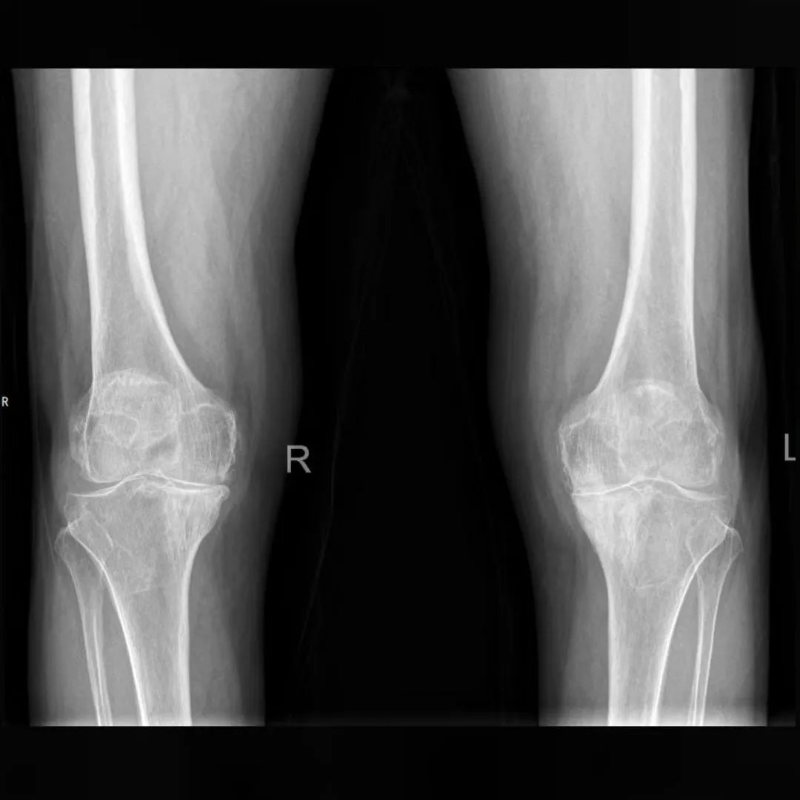

70多歲的葉阿姨,被膝關(guān)節(jié)骨關(guān)節(jié)炎困擾多年,就診時雙側(cè)膝關(guān)節(jié)已明顯畸形,無法正常行走,病變嚴(yán)重到均需要行人工膝關(guān)節(jié)置換,而癥狀更重的一側(cè),CT顯示脛骨平臺下方有一巨大骨囊腫,所以對于平臺假體的安放成了棘手的問題,通過AI術(shù)前規(guī)劃很好的解決了這個問題,規(guī)劃能明確截骨的厚度,獲知囊腫的范圍從而提前做好處理預(yù)案,進(jìn)而確定選擇合適的假體,術(shù)中基本按規(guī)劃和預(yù)案進(jìn)行,假體安放順利,安放牢固。患者術(shù)后第二天就能下床活動,出院時對手術(shù)效果很是滿意,已經(jīng)預(yù)約三個月后再做另一側(cè)關(guān)節(jié)的手術(shù)。

文章配圖

△術(shù)前